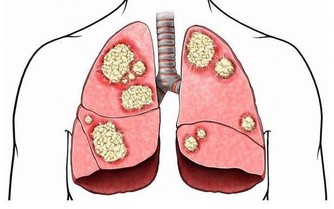

2、自測肺功能:憋氣

深吸一口氣後憋氣,如果能憋氣達30秒以上,表明心肺功能很好;能憋氣達20秒以上者也不錯。20秒以下的人群建議日常要有意識地對肺部進行保養,如戒菸、適當進行運動鍛煉等。